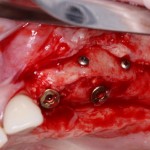

Устанавливается имплантат Astratech (Dentsply Implants):

Для аугментации также используем Bio-Oss Collagen 100 mg, нарезаем его по размеру с помощью скальпеля и позиционируем в лунках щечных корней:

На имплантат ставим формирователь, ушиваем лунку. Напомню, что любой биоматериал должен быть герметично запечатан в ране (фактор успеха III). В противном случае, от него больше вреда, чем пользы: